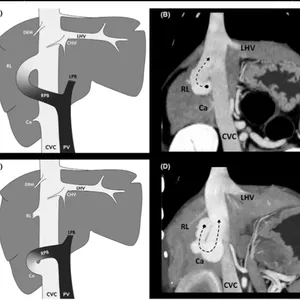

▶️ Anatomofisiologia: Adquira conhecimento aprofundado sobre a anatomia e a fisiologia envolvidas no Shunt Portossistêmico.

▶️ Diagnóstico avançado: Aprenda a utilizar ferramentas diagnósticas de última geração para uma avaliação precisa.

▶️ Planejamento cirúrgico: Desenvolva habilidades para planejar estrategicamente cada procedimento.

▶️ Procedimento cirúrgico: Pratique a execução precisa e segura da cirurgia de Shunt Portossistêmico.